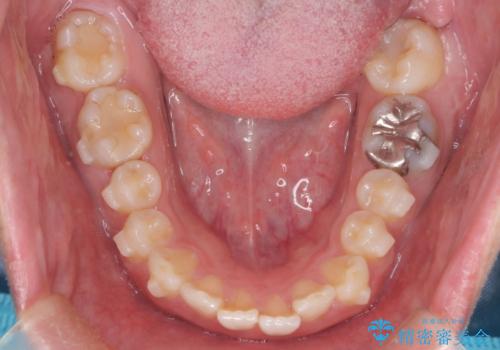

- 前歯の隙間と口元を主訴に来院されました。

インビザラインにて治療を行いきれいな歯並びをつくることができました。

奥歯の噛み合わせもきちんと仕上げることができました。